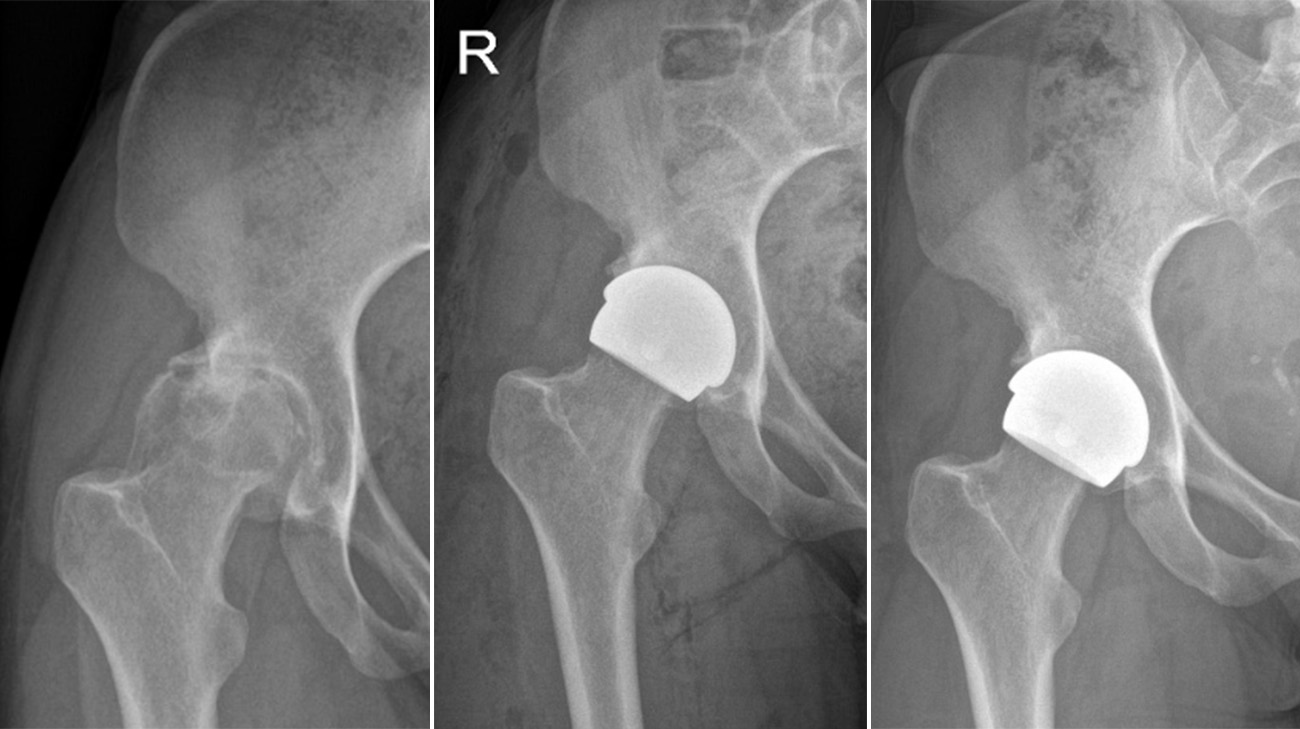

Georgina's hip joint before and after surgery with the ceramic hip resurfacing in place. The X-rays show the pelvis and spine returning to alignment. (Courtesy: Cleveland Clinic)

Instead of replacing the entire hip joint, a resurfacing surgery involves replacing only the hip socket with a prosthetic piece. The ceramic implant Georgina received is tailored specifically for patients with smaller hips and pelvises. (Courtesy: Cleveland Clinic)

Georgina came to Prof Cobb at the right time. For years, the only available option was metal-on-metal hip resurfacing, which manufacturers currently recommend only for patients with larger femoral heads – typically found more often in men. This design is less suitable for individuals with smaller bone structures, including many women and others with narrower hips, who are more likely to experience pain and require early revision after the procedure. In response to this limitation, Prof Cobb and a team of developers created an innovative ceramic hip resurfacing implant called the H1, tailored specifically for patients with smaller hips and pelvises.